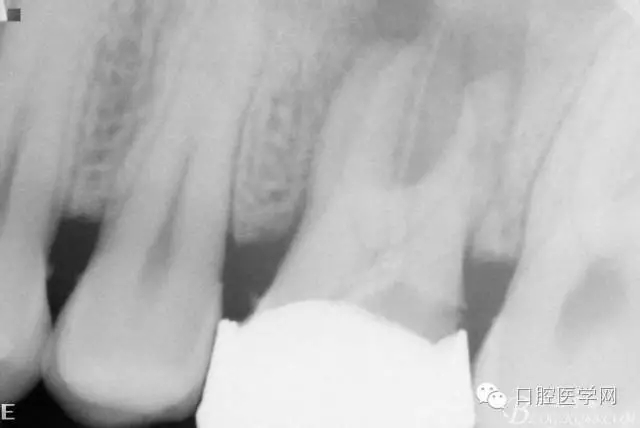

檢查26Ⅲ°松動(dòng)(頰舌向、近遠(yuǎn)中向、頜齦向)。X線片顯示根尖周彌漫性炎性陰影。

初診X線片